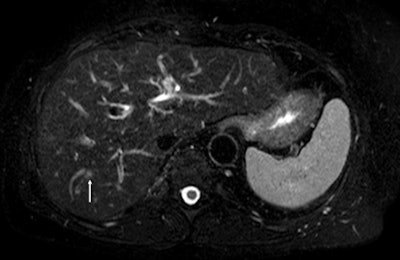

On the diffusion-weighted image, the same lesion is seen as well as two additional metastases: one in the right liver and one in the left liver. All metastases are strongly hyperintense compared to the background liver at b = 600 sec/mm2, indicating restricted diffusion. All of these lesions were surgically confirmed as metastases.Future trends in intra-arterial therapy of liver malignancies were outlined by Dr. Thierry de Baere, from the department of interventional radiology at the IGR. In the intra-arterial treatment of hepatocellular carcinoma, 3D angiography guidance with computer image analysis can improve outcomes of chemoembolization by better depicting liver tumors. Tumor feeding vessels can be depicted with a sensitivity of 93%, with the main limitation being in vessels smaller than 1 mm or when patients have been treated already, he explained.